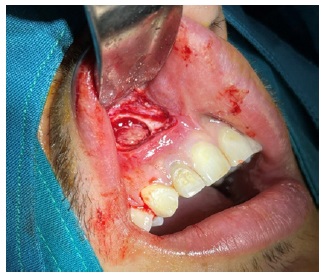

Obteniendo como diagnóstico presuntivo un quiste radicular asociado a la pieza 1.2; se le solicitó al paciente una biometría hemática, con todos los valores dentro de parámetros normales; se realizó el procedimiento quirúrgico de descompresión, por medio de una incisión lineal, el levantamiento del colgajo mucoperiostico y posterior osteotomía a nivel del ápice de la pieza 1.2, hasta descubrir la membrana del quiste (figura 3a), se extiende la ventana con un diámetro de aproximadamente 5 mm compatible con el diámetro del dren que colocaríamos, se realizó una incisión a nivel de la membrana del quiste y se drenó líquido seropurulento, se realiza el lavado mediante el orificio, con suero fisiológico y yodopovidona (Figura 3b).

Figura 3a Se observa ventana de 5 mm de diámetro que se realizó mediante osteotomía a nivel del ápice de la pieza 1.2; observamos la membrana del quiste.